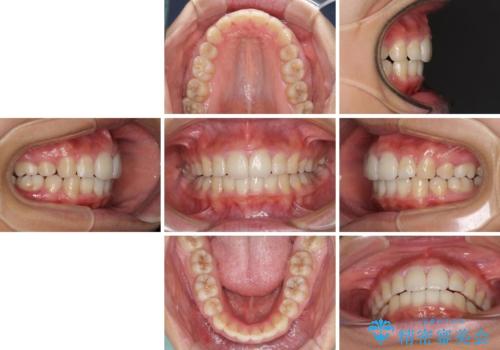

口が閉じられない 抜歯矯正で口元をスッキリと

しっかりと通院するようになってからは順調に治療が進み、横顔の印象が変わるほどスッキリとした口元となりました。